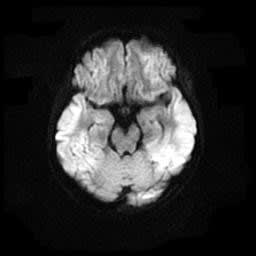

低酸素脳症の画像 なんでも内科診療日誌